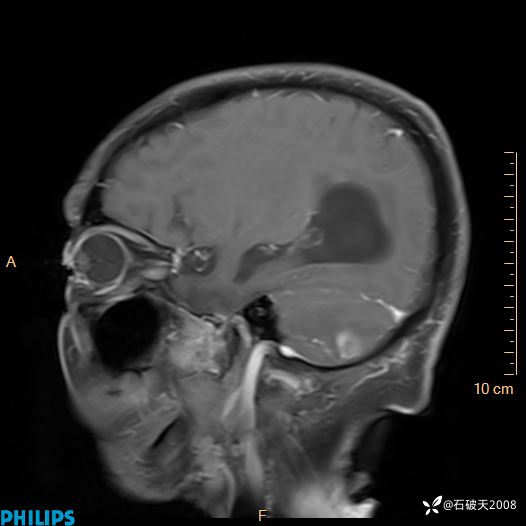

书上说这个肿瘤发生在幕下仅4.09%,你会想到它吗?(病理已公布)

女 86岁 主 诉:乏力1月

现病史:患者1月前活动出现双下肢乏力,无头晕、头痛、恶心、呕吐、肢体活动不利,休息后缓解,间断断发作,症状进行性加重,在家口服药物治疗(具体不详),效差,为进一步诊治,来我院,门诊按“乏力”收住我科,患者自发病以来,神志清,精神稍差,饮食睡眠欠佳,大小便正常,体重未见明显改变。

DWI

增强矢状位